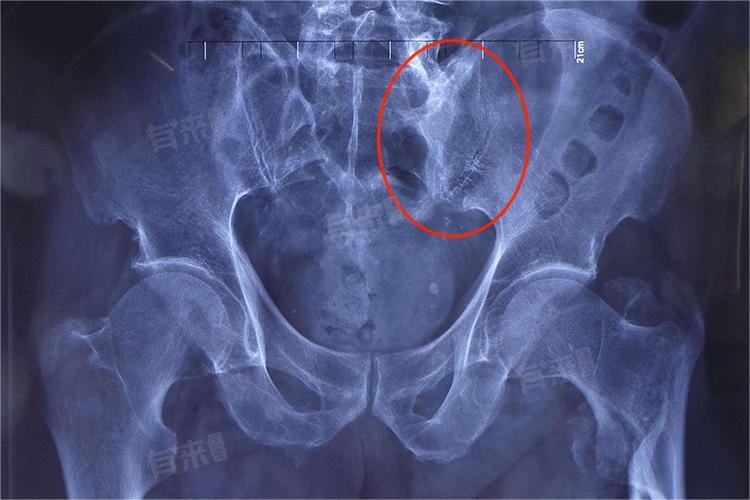

- 6周左右时,若通过影像学检查显示骨折愈合良好,可在医生指导下逐渐坐起,并借助辅助器具如轮椅等进行适当活动,但此时还不能完全负重。一般在8到10周,可尝试部分负重下地行走,如使用双拐,患肢轻轻着地,逐渐增加负重的时间和力量。经过一段时间的适应和锻炼,在10到12周时,部分患者可以尝试完全负重,正常下地行走。

- 一般在术后6到8周,复查显示骨折有初步愈合迹象后,可在助行器或双拐辅助下开始部分负重行走练习。随着骨折的进一步愈合,在术后8到12周,根据骨折愈合的具体情况,逐渐过渡到完全负重,正常下地行走,但这个过程需要在医生的指导下,通过多次复查和评估来确定。